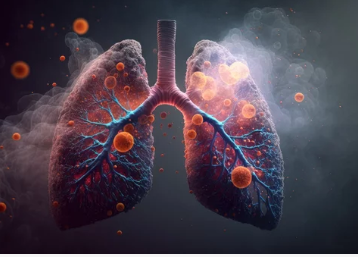

폐결핵은 **결핵균(Mycobacterium tuberculosis)**이 폐에 감염되어 염증을 일으키는 질환입니다. 과거에는 ‘잊혀진 질병’이었지만, 최근 면역 저하자와 고령 인구 증가로 인해 다시 증가하는 추세입니다. 감기와 유사한 증상으로 시작하지만, 몇 주 이상 기침이 계속되거나 밤에 식은땀이 나는 경우는 반드시 결핵을 의심해봐야 합니다. 이 글에서는 폐결핵의 주요 증상, 전염성 여부, 진행 양상까지 상세히 정리해드립니다.